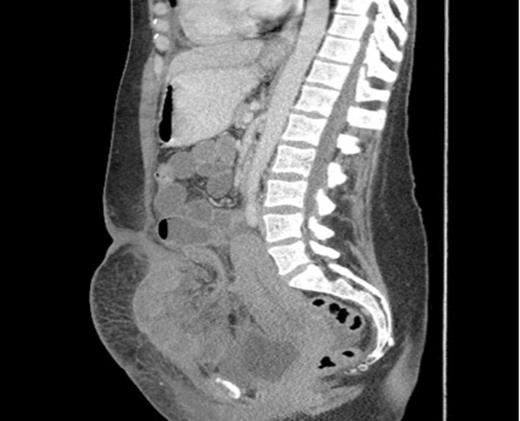

Sagittal section showing dilated loops of small bowel and a segment of small bowel adherent to the anterior abdominal wall.